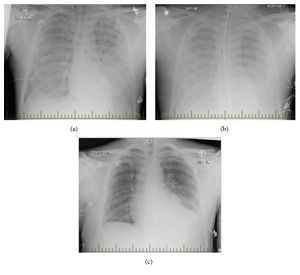

| Progression of hantavirus pulmonary syndrome | |

تكونُ الأعراض الأولية للمرض مُشابهةً لأعراض الإنفلونزا، وتتضمن حمى وسُعال وألم عضلي وصداع وخُمول وضيق في التنفس، والتي تتدهور بسرعةٍ إلى فشلٍ تنفسيٍ حاد. يتميزُ المرض بحدوث ضيقٍ فجائيٍ في التنفس مع وذمةٍ رئوية سريعة الظهور، وغالبًا ما تكون قاتلةً على الرغم من التهوية الميكانيكية واستعمال مُدرات البول القوية. تبلغ نسبة الوفيات حوالي 36%.